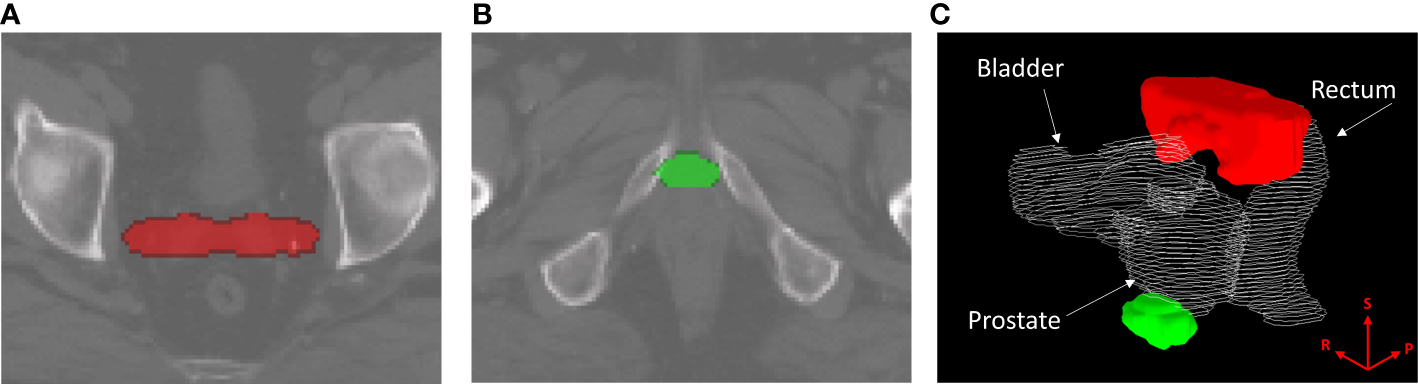

Binary-IBDM did not identify any regions where the dose distribution was significantly different between recur status within four-years of radiotherapy for patients treated with hypo-fractionated radiotherapy or IMRT. However, two regions were identified for patients who were treated with brachytherapy boost: one at the seminal vesicle tips (red overlay, Figures 1A, C), and one at the apex of the prostate (green overlay, Figures 1B, C).

Regions where the dose distribution was significantly different (p ≤ 0.02) between patients who did and did-not experience biochemical recurrence (BCR) within four years of radiotherapy, for patients treated with intensity modulated radiotherapy plus a single high dose rate brachytherapy boost. Regions are overlayed on the planning CT of the reference patient used for image registration and dose mapping, and indicate where excess dose was associated with lower BCR. The identified region in (A), marked in red, corresponds with the seminal vesicle tips. The region in (B), marked in green, corresponds to the apex region of the prostate. (C) shows the two regions in relation to the prostate, rectum and bladder of the reference patient. The superior (S), right (R) and posterior (P) directions are indicated on the render in (C).